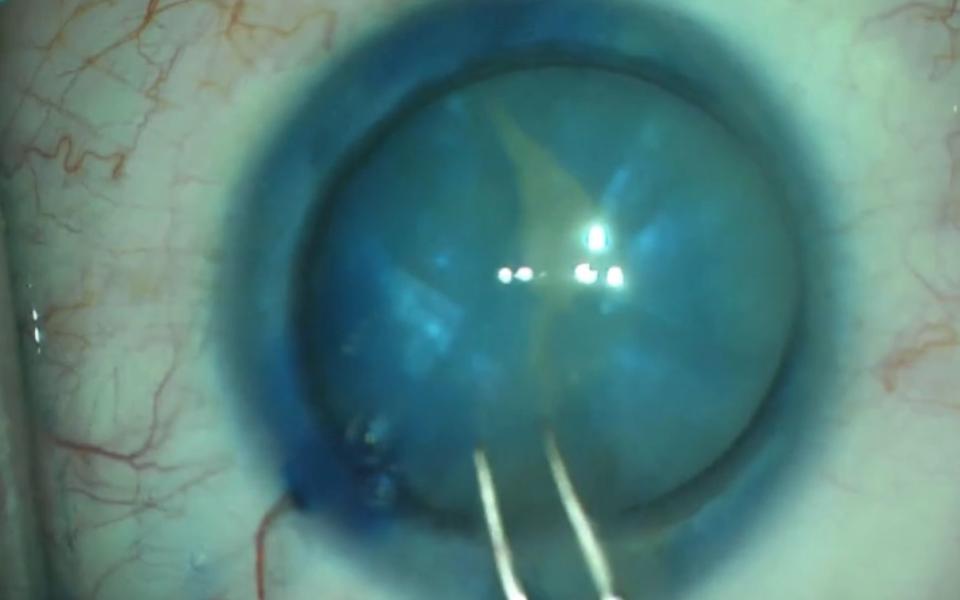

The Argentinan Flag sign more commonly occurs in patients with mature nuclear sclerosis. The anterior capsule is stained with trypan blue (Vison Blue). When the capsule is decompressed with a 25G